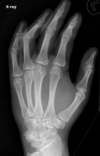

Fratura de Bennett

Fratura da base do primeiro metacarpo;

Intra-articular;

Dois fragmentos.